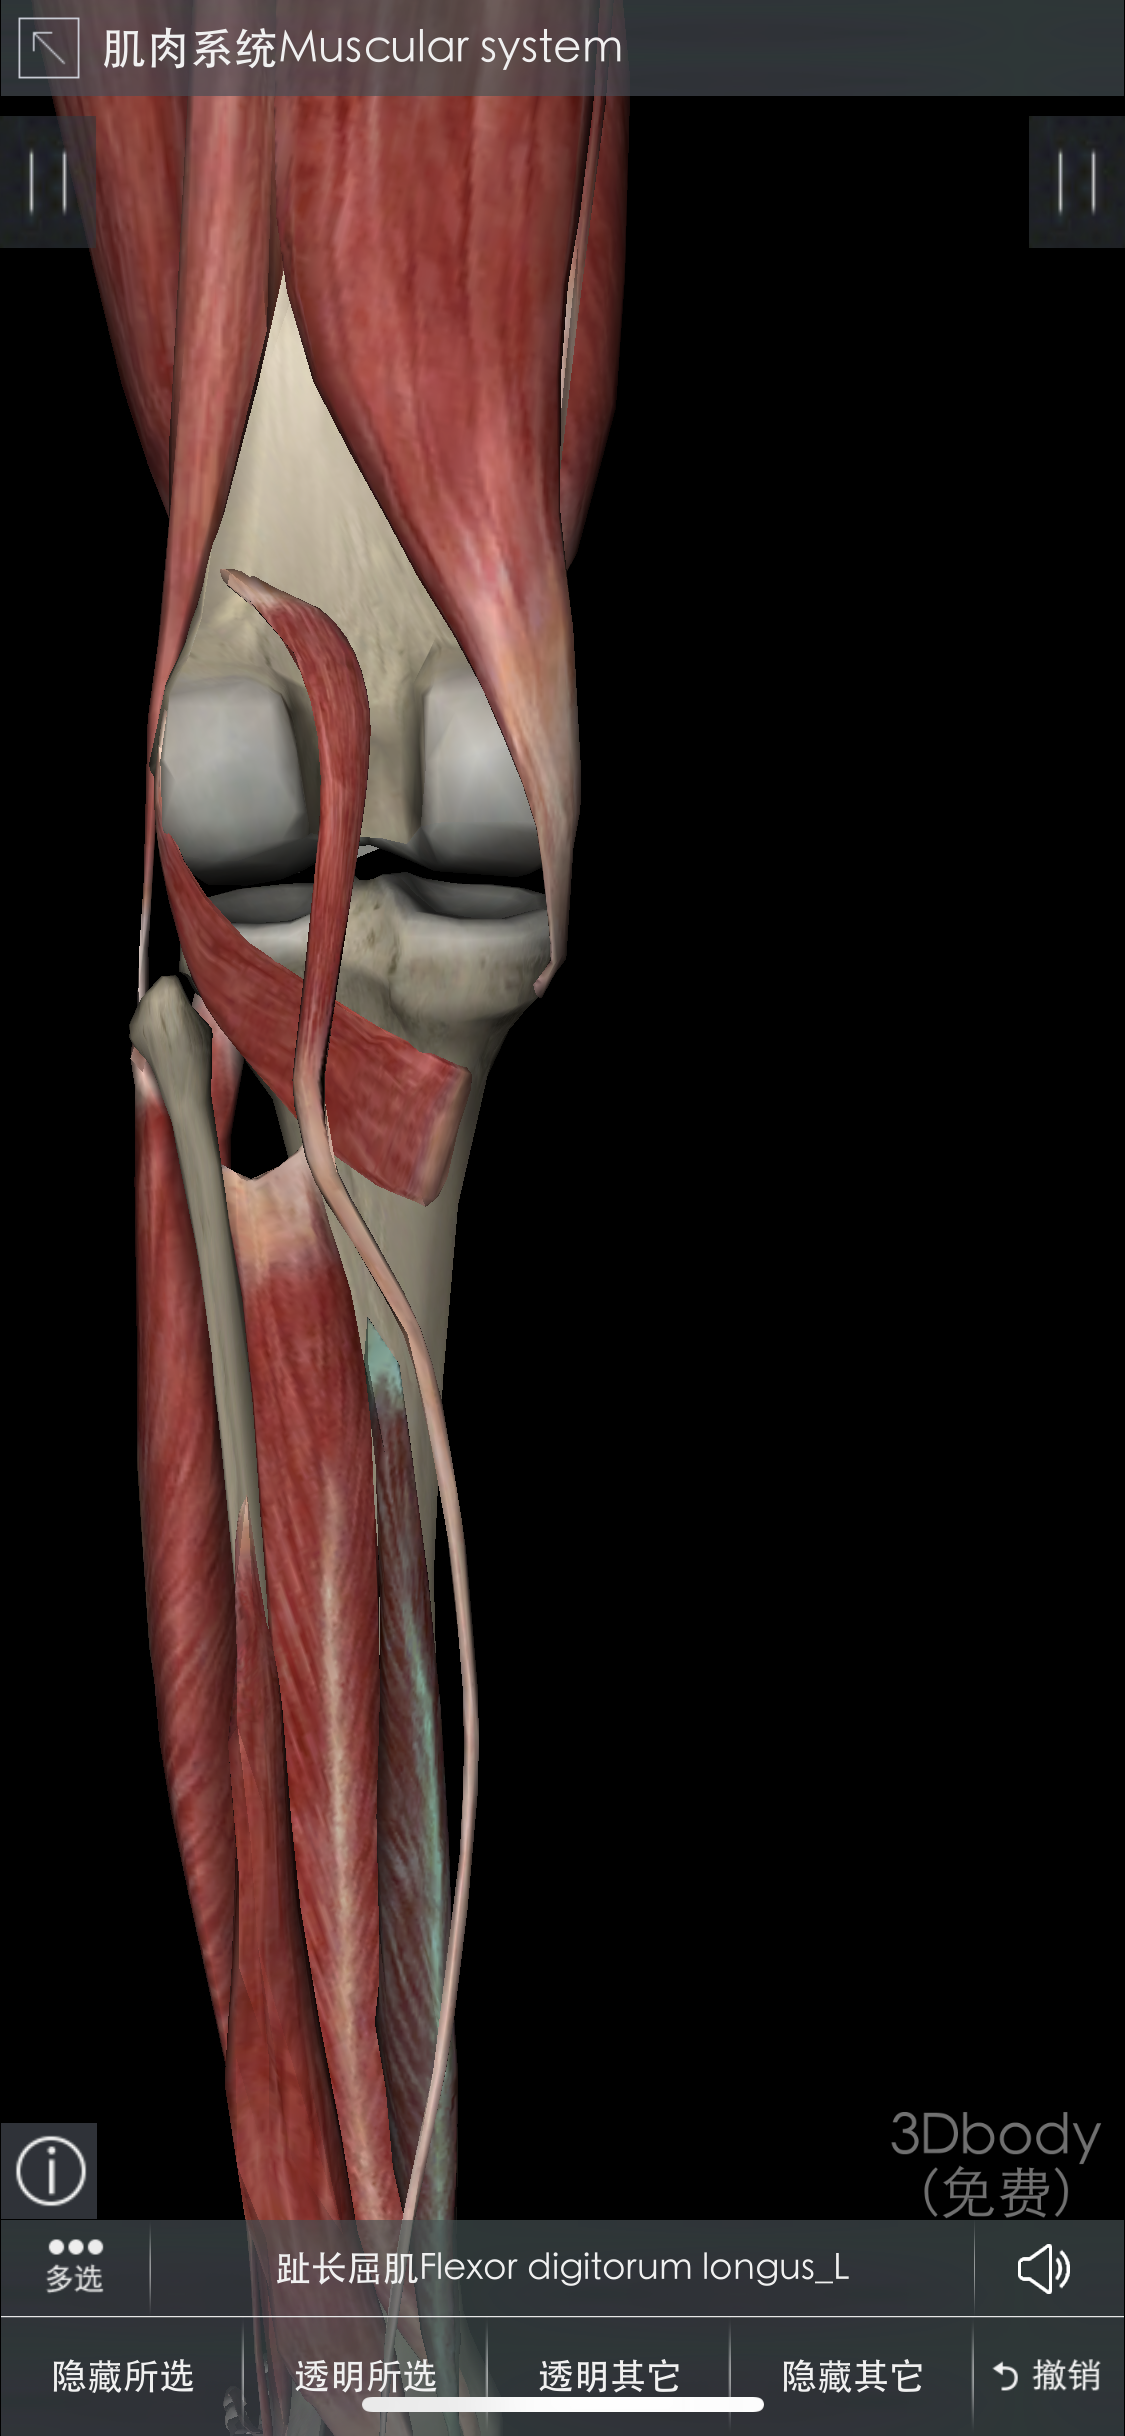

脛骨近位端骨折は,膝 関節内および周辺部の骨折で あり,関節面の不適合性や不安定性内外反変形を残し やすく,治療に配慮を要する骨折である 今回,我 々は,当 院における脛骨近位端骨折の手術 症例について検討したので,そ の治療成績および治療下腿骨骨折(脛骨骨折、腓骨骨折)の基礎知識 point 下腿骨骨折(脛骨骨折、腓骨骨折)とは すねの骨は脛骨と腓骨の2本からなりますが、下腿骨骨折はそのうち一方または両方が骨折することで、交通事故やスポーツ、転倒が原因で起こることが多いです。解剖学的には、足関節は脛骨、腓骨、距骨の3つの骨で構成され、足関節の内果と後果は脛骨の遠位部にあたり、足関節外果は腓骨遠位部にあたります。 これらをまとめた代表的なものにLaugeHansenの分類(図)があります。 外果の横骨折が生じ

POINT 下腿骨骨折(脛骨骨折、腓骨骨折)とは すねの骨は脛骨と腓骨の2本からなりますが、下腿骨骨折はそのうち一方または両方が骨折することで、交通事故やスポーツ、転倒が原因で起こることが多いです。 骨折した部分は腫れや痛み、内出血がみられます。 レントゲン検査やCT検査などの画像検査によって骨折の部位や程度が調べられます。 骨折の程度によっAO/OTA分類 続いて、もう少し詳しい分類についてまとめていきます。 AO/OTA分類 は、骨盤後方部の損傷程度(部分破綻・完全破綻)から骨盤輪の安定性により分類しています。 Pannal分類では、骨折を生じる際に加わった外力の方向を、前後方向の圧迫(anteroposterior compression)、側方からの圧迫今回は脛骨高原骨折について、 まるごと理解してしまおう! ということで、専門医の視点を 少しでもわかりやすく、噛み砕いて 解説いたします。 こんにちは、スポーツ整形外科医の歌島です。 本

概念とか分類とか 脛骨粗面の骨折ですが、 病態としては "膝蓋腱による脛骨粗面への牽引力によって生じる" です。 脛骨粗面への二次骨化核が周囲と癒合する年齢に好発します。 大体男女とも1316歳ぐらいです。 多いのは男児!骨折の分類 ②部位による分類 ③形状などによる分類 骨折の分類 ④外部との交通の有無による分類 皮下骨折(closed fracture)→単純骨折 骨折部に創がない or あっても骨折部と直接つながっていないもの 開放骨折(open fracture) →複雑骨折 皮膚に創があっ脛骨近位端骨折の分類と骨癒合までの期間 脛骨近位端骨折は高原骨折やプラトー骨折とも呼ばれます。 プラトーは英語で「高原」のことで、関節面の形を例えているとされています。 荷重関節の関節内骨折であり、半月板損傷や靭帯損傷を合併しやすい